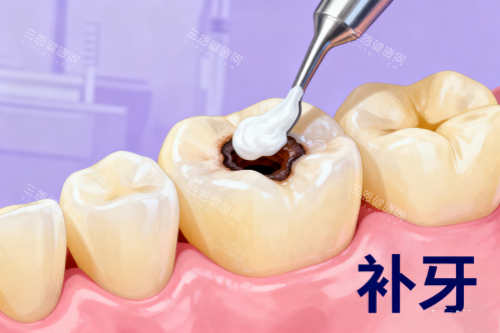

接下来就是补牙了,张医生先给我做了局部麻醉,他说“可能会有点胀胀的感觉,别害怕”。麻醉起效后,他用正规的工具清理蛀坏的部分,过程中会时不时问我“疼不疼?有不舒服就举手”。我本来还担心会有刺耳的声音,结果发现他们用的器械噪音特别小,而且护士一直在旁边帮我吸口水,递工具,服务特别周到。

清理完蛀洞后,张医生给我看了几种补牙材料,有树脂的、玻璃材料的,还有进口的纳米树脂。他详细介绍了每种材料的优缺点:“树脂材料颜色和牙齿很接近,硬度也够,适合补后牙;玻璃材料对牙齿刺激小,适合儿童或者敏感牙;进口纳米树脂更耐磨,使用寿命更长。”他还根据我的情况推荐了树脂材料,说性价比较高,价格也在我的预算范围内。

选好材料后,张医生就开始填充了。他特别细致,填充完还会用工具一点点塑形,打磨,直到和我的牙齿形状完全贴合。补完后,他让我咬合几下,问我“有没有高低不平的感觉?”,调整到合适的高度后,又用光照固化,整个过程大概也就二十多分钟。